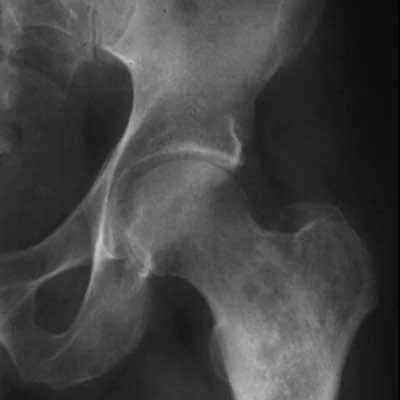

Bone cancer is uncommon, accounting for less than 1% of all cancer cases diagnosed each year. Osteosarcoma is the most common type of primary bone cancer, affecting mostly children and young adults. Other types of primary bone cancers include chondrosarcoma and Ewing sarcoma.

Osteosarcoma is the most common type of bone cancer, accounting for roughly three out of every four cases. It is most commonly found in the long bones of the arms and legs, such as the femur and tibia. Osteosarcoma is most common in children and young adults, with a median age of diagnosis of 15 years. Osteosarcoma is typically treated with surgery to remove the tumour, followed by chemotherapy.